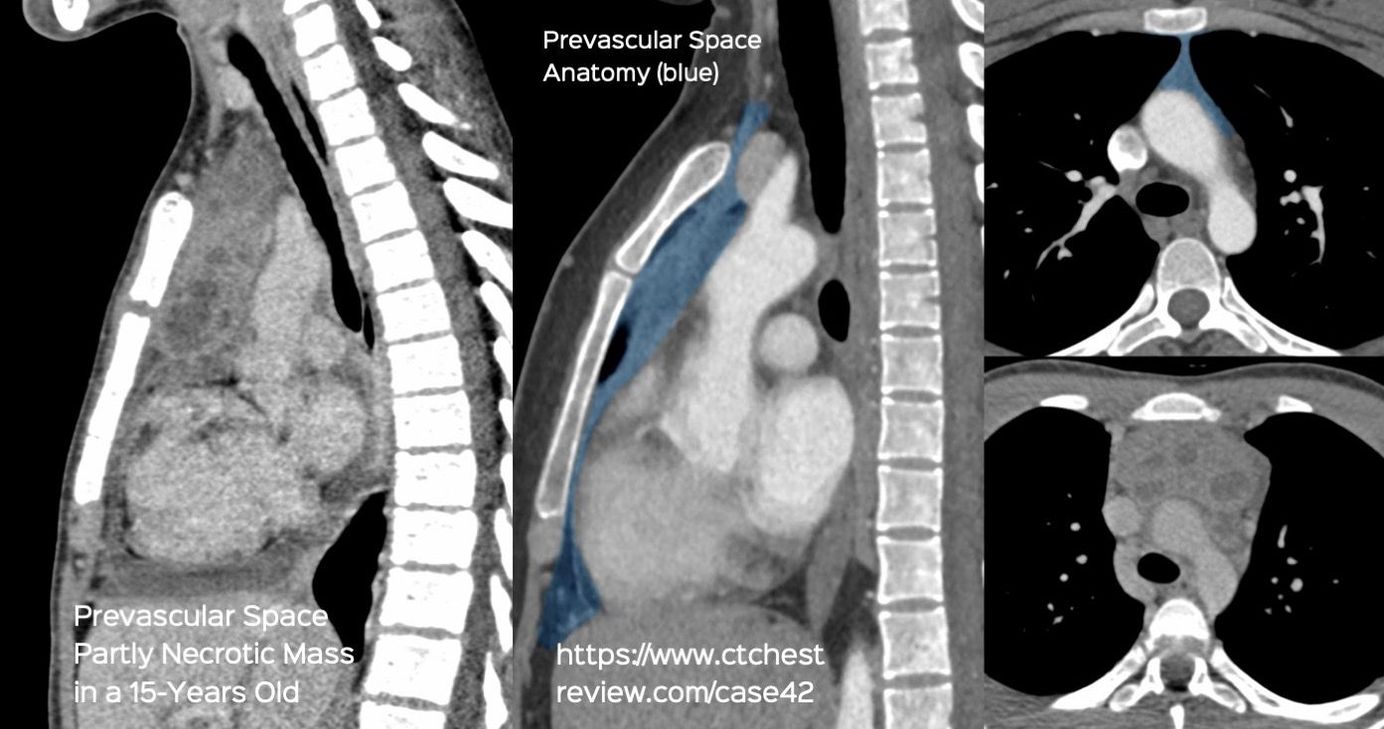

Case 42: Every Necrotic Mass in the Prevascular Space of the Mediastinum is NOT Tuberculosis Members Public

Every Necrotic Mass in the Prevascular Space of the Mediastinum is NOT Tuberculosis